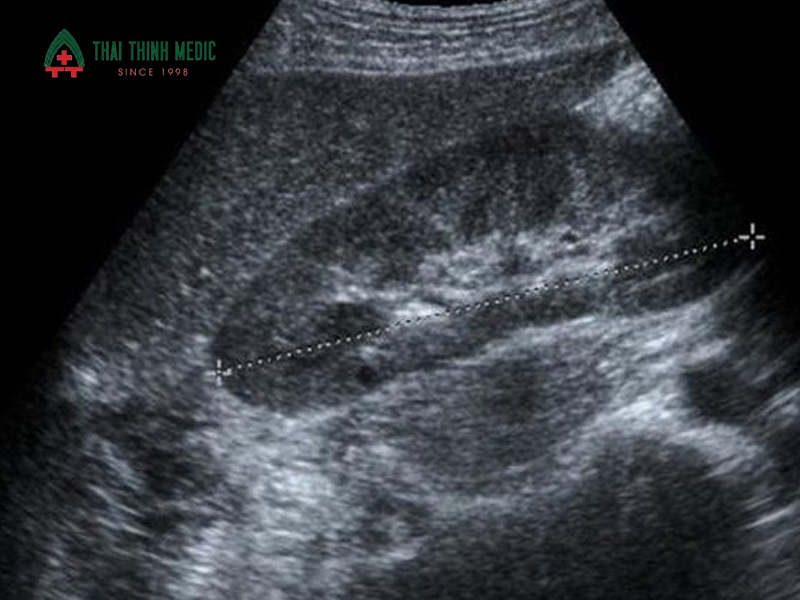

Thông qua các hình ảnh siêu âm, bác sĩ có thể quan sát được cấu trúc nhu mô gan, mức độ phản xạ sóng và mỗi tương quan giữa gan với các cơ quan lân cận như thận và lách. Từ đó, những dấu hiệu đặc trưng của gan nhiễm mỡ sẽ được phát hiện sớm, giúp người bệnh kịp thời điều chỉnh lối sống hoặc điều trị, hạn chế nguy cơ tiến triển thành viêm gan nhiễm mỡ hoặc xơ gan.

Các dấu hiệu gan nhiễm mỡ thường thấy trên siêu âm:

- Tăng độ hồi âm của nhu mô gan: Gan có hình ảnh sáng hơn bình thường do mỡ tích tụ nhiều trong tế bào gan, đây là dấu hiệu phổ biến nhất của gan nhiễm mỡ trên siêu âm.

- Gan sáng hơn thận hoặc lách: Khi so sánh trên cùng mặt cắt, độ sáng của gan vượt trội so với thận phải hoặc lách, gợi ý tình trạng nhiễm mỡ.

- Giảm khả năng xuyên âm của sóng siêu âm: Sóng siêu âm khó xuyên sâu vào nhu mô gan, khiến hình ảnh các cấu trúc phía sau gan mờ hơn.

- Bờ gan tròn, kích thước gan to hơn bình thường: Một số trường hợp gan nhiễm mỡ có thể kèm theo gan to nhẹ.

- Hình ảnh mạch máu trong gan kém rõ: Các tĩnh mạch gan và tĩnh mạch cửa có thể bị che khuất do tăng hồi âm nhu mô.

Gan nhiễm mỡ độ 2 là giai đoạn trung bình, trong đó lượng mỡ tích tụ trong gan nhiều hơn và đã ảnh hưởng rõ đến cấu trúc nhu mô gan. Trên siêu âm, gan tăng hồi âm rõ rệt, sáng hơn đáng kể so với thận hoặc lách. Khả năng xuyên âm của sóng siêu âm bắt đầu giảm, khiến hình ảnh các cấu trúc sâu trong gan và các mạch máu gan trở nên mờ hơn.